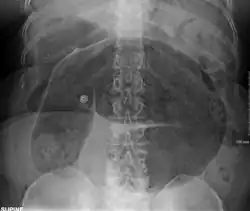

Coffee bean sign in a person with sigmoid volvulus -